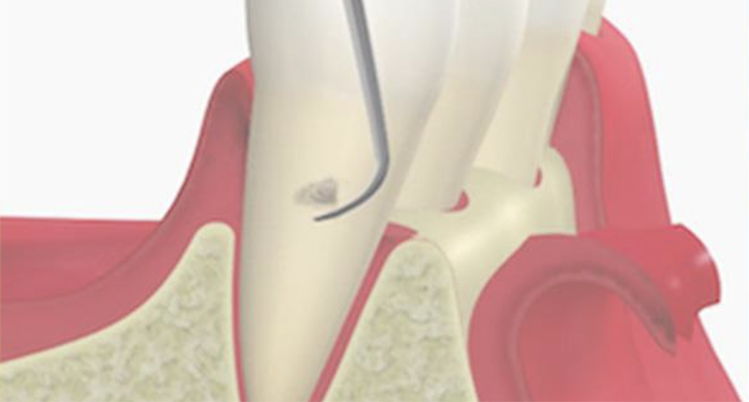

3. SRP

(スケーリング・ルートプレーニング)

専用の器具を使って、歯ぐきの中にある汚れを除去して、歯の根っこ部分の表面を汚れの付着が起こりにくい状態に仕上げる処置です。

主に、歯ぐきの中にまで歯石が入り込んでいる中等度以上の患者さまに対して行います。痛みが強い場合は、麻酔をして行うこともあります。

歯と歯茎の間の汚れをかき出すイメージイラスト

4. 歯周ポケット掻爬術

歯ぐきの内側の炎症をおこしている組織を取り除く処置です。

麻酔の効いている状態で行うため、治療中の痛みはほとんどありません。

内側からの炎症改善を目的としており、清潔になった歯の根に歯ぐきが付着し、汚れが溜まりにくい環境を作ることができます。

歯周ポケット掻爬術のイメージイラスト